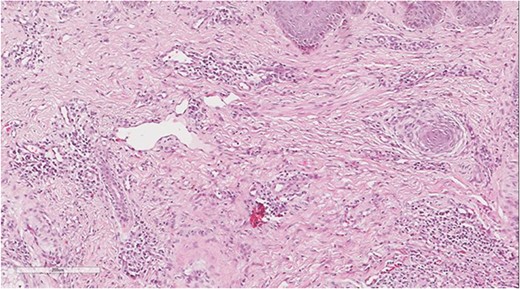

A 5 mm skin punch biopsy was also taken from the neck. Histopathology showed cystically dilated hair follicle with surrounding fibrosis and heavy inflammatory infiltrate and granulation tissue (Fig. 1), the inflammatory infiltrate is composed of lymphocytes, plasma cells, neutrophils and histiocytes (Fig. 2). The overall morphologic picture was suggestive of follicular occlusion syndrome (Fig. 3). A diagnosis of HS was made, and the patient was started on rifampin 600 mg OD and clindamycin 300 mg BID. A lipid panel was ordered as well and showed a triglyceride level of 1.99 mmol/L (0.7–1.7 mmol/L).

Dilated hair follicle with perifollicular inflammation and adjacent foreign body giant cell reaction secondary to ruptured dilated hair follicle in a background of dermal fibrosis.